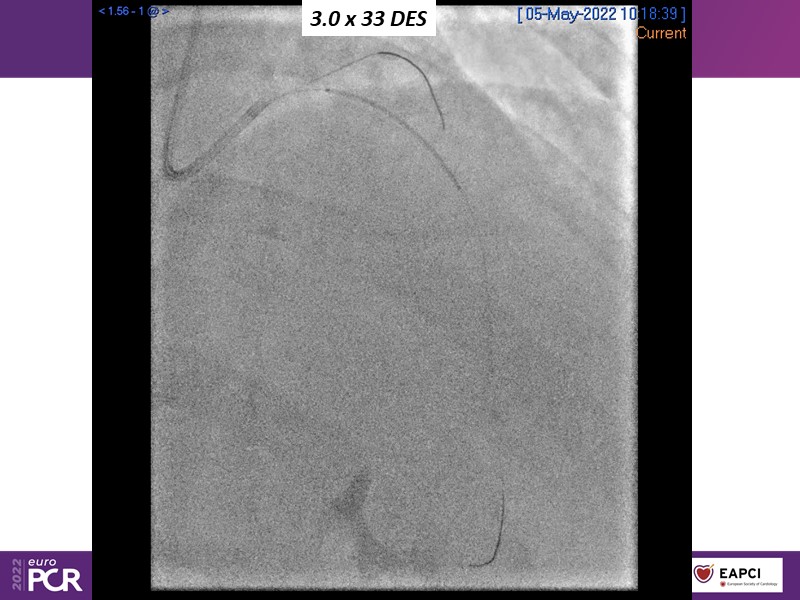

Alexandre Abizaid, Marco Valgimigli, Fazila Malik, Luca Testa, Patrick W. Serruys, Damiano Regazzoli, Kumar Prathap, and Sandeep Basavarajaiah take turns in this session to discuss two innovative technologies: a stent platform with nanotechnology and a novel drug-coated balloon (DCB). These novel technologies both have unique features that could change daily practice and improve outcomes.

- To understand how useful is a DES and DCB stent platform in complex coronary artery disease settings with case demonstrations and follow-up in diabetes mellitus